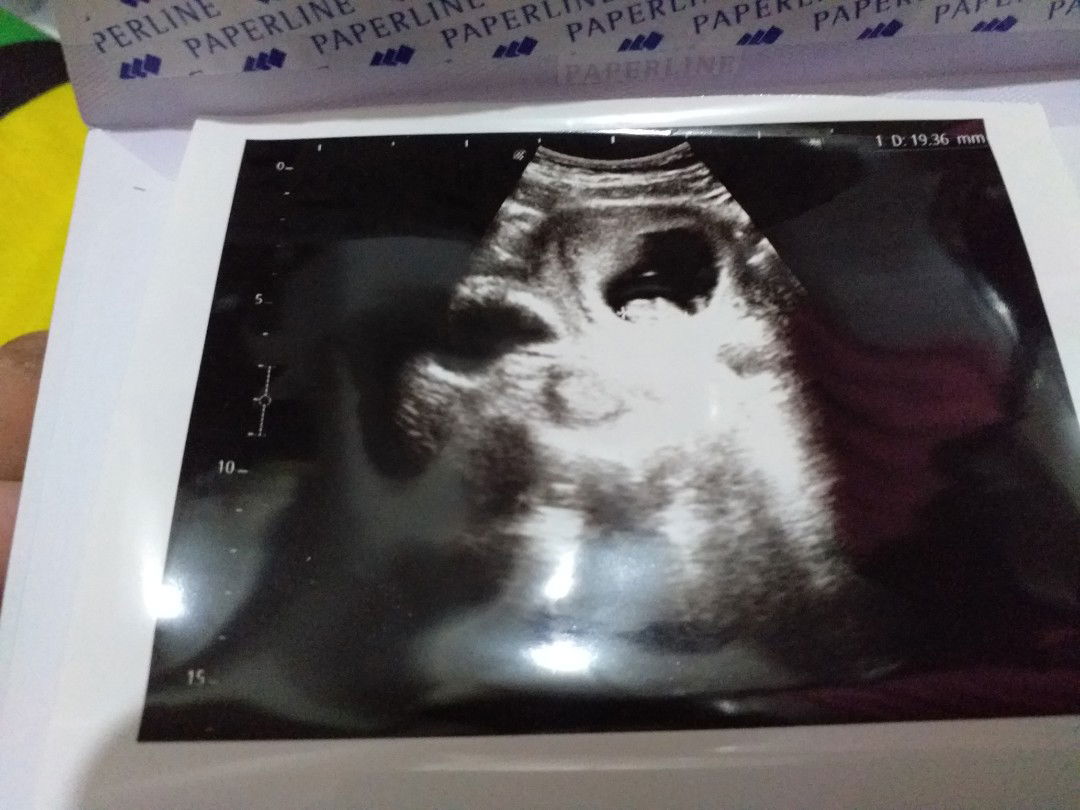

usg yang ke 3

19wek2d .. seneng banget liahat wajah mu dek . Mulutnya juga bisa nesu??